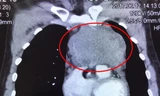

Theo Ths.BS Ngô Đức Hiệp-Trưởng khoa Phỏng-Phẫu thuật tạo hình BV Chợ Rẫy, ngoài khối bướu máu nhìn thấy bằng mắt thường ở vùng đầu mặt (10x15cm), bên trong não bệnh nhân T còn một khối bướu khác ước lớn nhất chiếm khoảng 20-25% diện tích hộp sọ.

BS Hiệp giải thích do không thể xác định được hai khối bướu máu có thông nhau hay không. Nếu thông nhau, khi phẫu thuật khối bướu bên ngoài sẽ tác động đến khối bướu bên trong, gia tăng áp suất nội sọ, khiến bệnh nhân đối mặt nguy cơ tử vong cao.